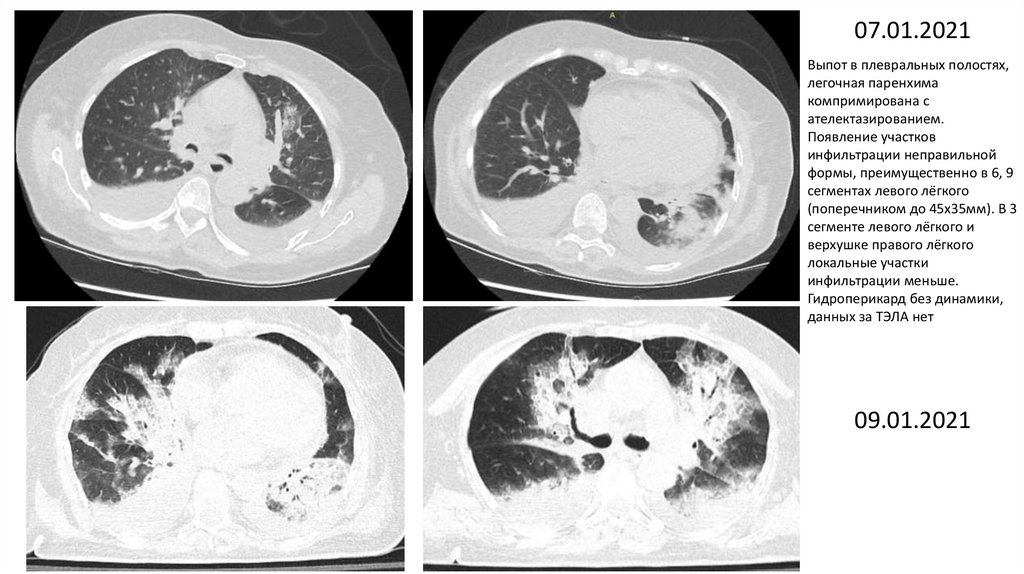

07.01.2021

Выпот в плевральных полостях,

легочная паренхима

компримирована с

ателектазированием.

Появление участков

инфильтрации неправильной

формы, преимущественно в 6, 9

сегментах левого лёгкого

(поперечником до 45х35мм). В 3

сегменте левого лёгкого и

верхушке правого лёгкого

локальные участки

инфильтрации меньше.

Гидроперикард без динамики,

данных за ТЭЛА нет

09.01.2021